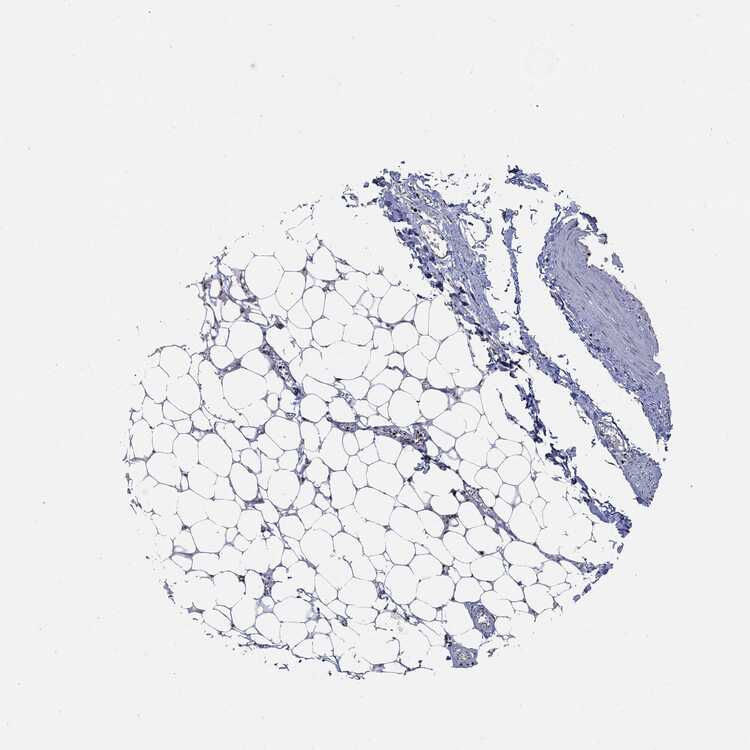

SOFT TISSUE 1 - Antibody stainingi

Antibody staining in the annotated cell types in the current human tissue is reported as not detected, low, medium, or high, based on conventional immunohistochemistry profiling in selected tissues. This score is based on the combination of the staining intensity and fraction of stained cells.

Each image is clickable and will lead to virtual microscopy that enables deeper exploration of all samples and also displays staining intensity scores, fraction scores and subcellular localization as well as patient and tissue information for each sample.

SOFT TISSUE 2 - Antibody stainingi